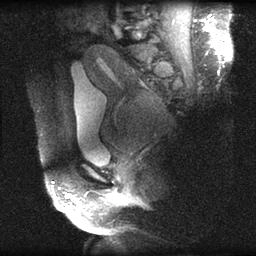

U xơ tử cung ở cổ tử cung (Leiomyoma of the uterine cervix)

16/03/2026